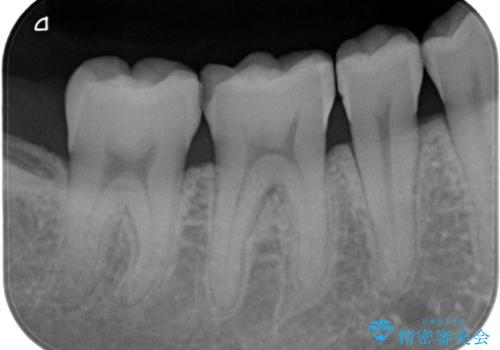

- 矯正終了後、昔詰めたプラスチックのやりかえを御希望されて3本セラミックにて治療を行いました。

プラスチックは経年的に劣化していて、虫歯の原因になることが多くあります。

今回の患者様も、プラスチックが劣化し着色が気になるとのことでしたがセラミックになってかなり喜んでいただけました。